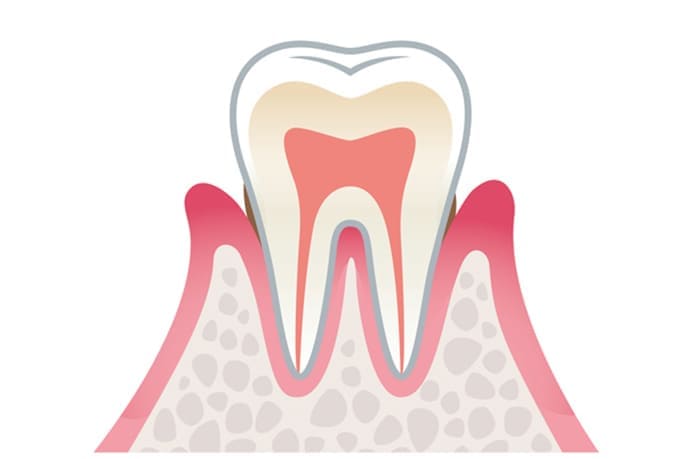

歯周病は、歯周病菌がつくり出す毒素などが原因で歯ぐきに炎症が起こる病気です。

進行すると、歯ぐきの内側にある歯根膜や歯槽骨といった歯を支える組織まで傷つき、放置すると最終的に歯を失うこともあります。